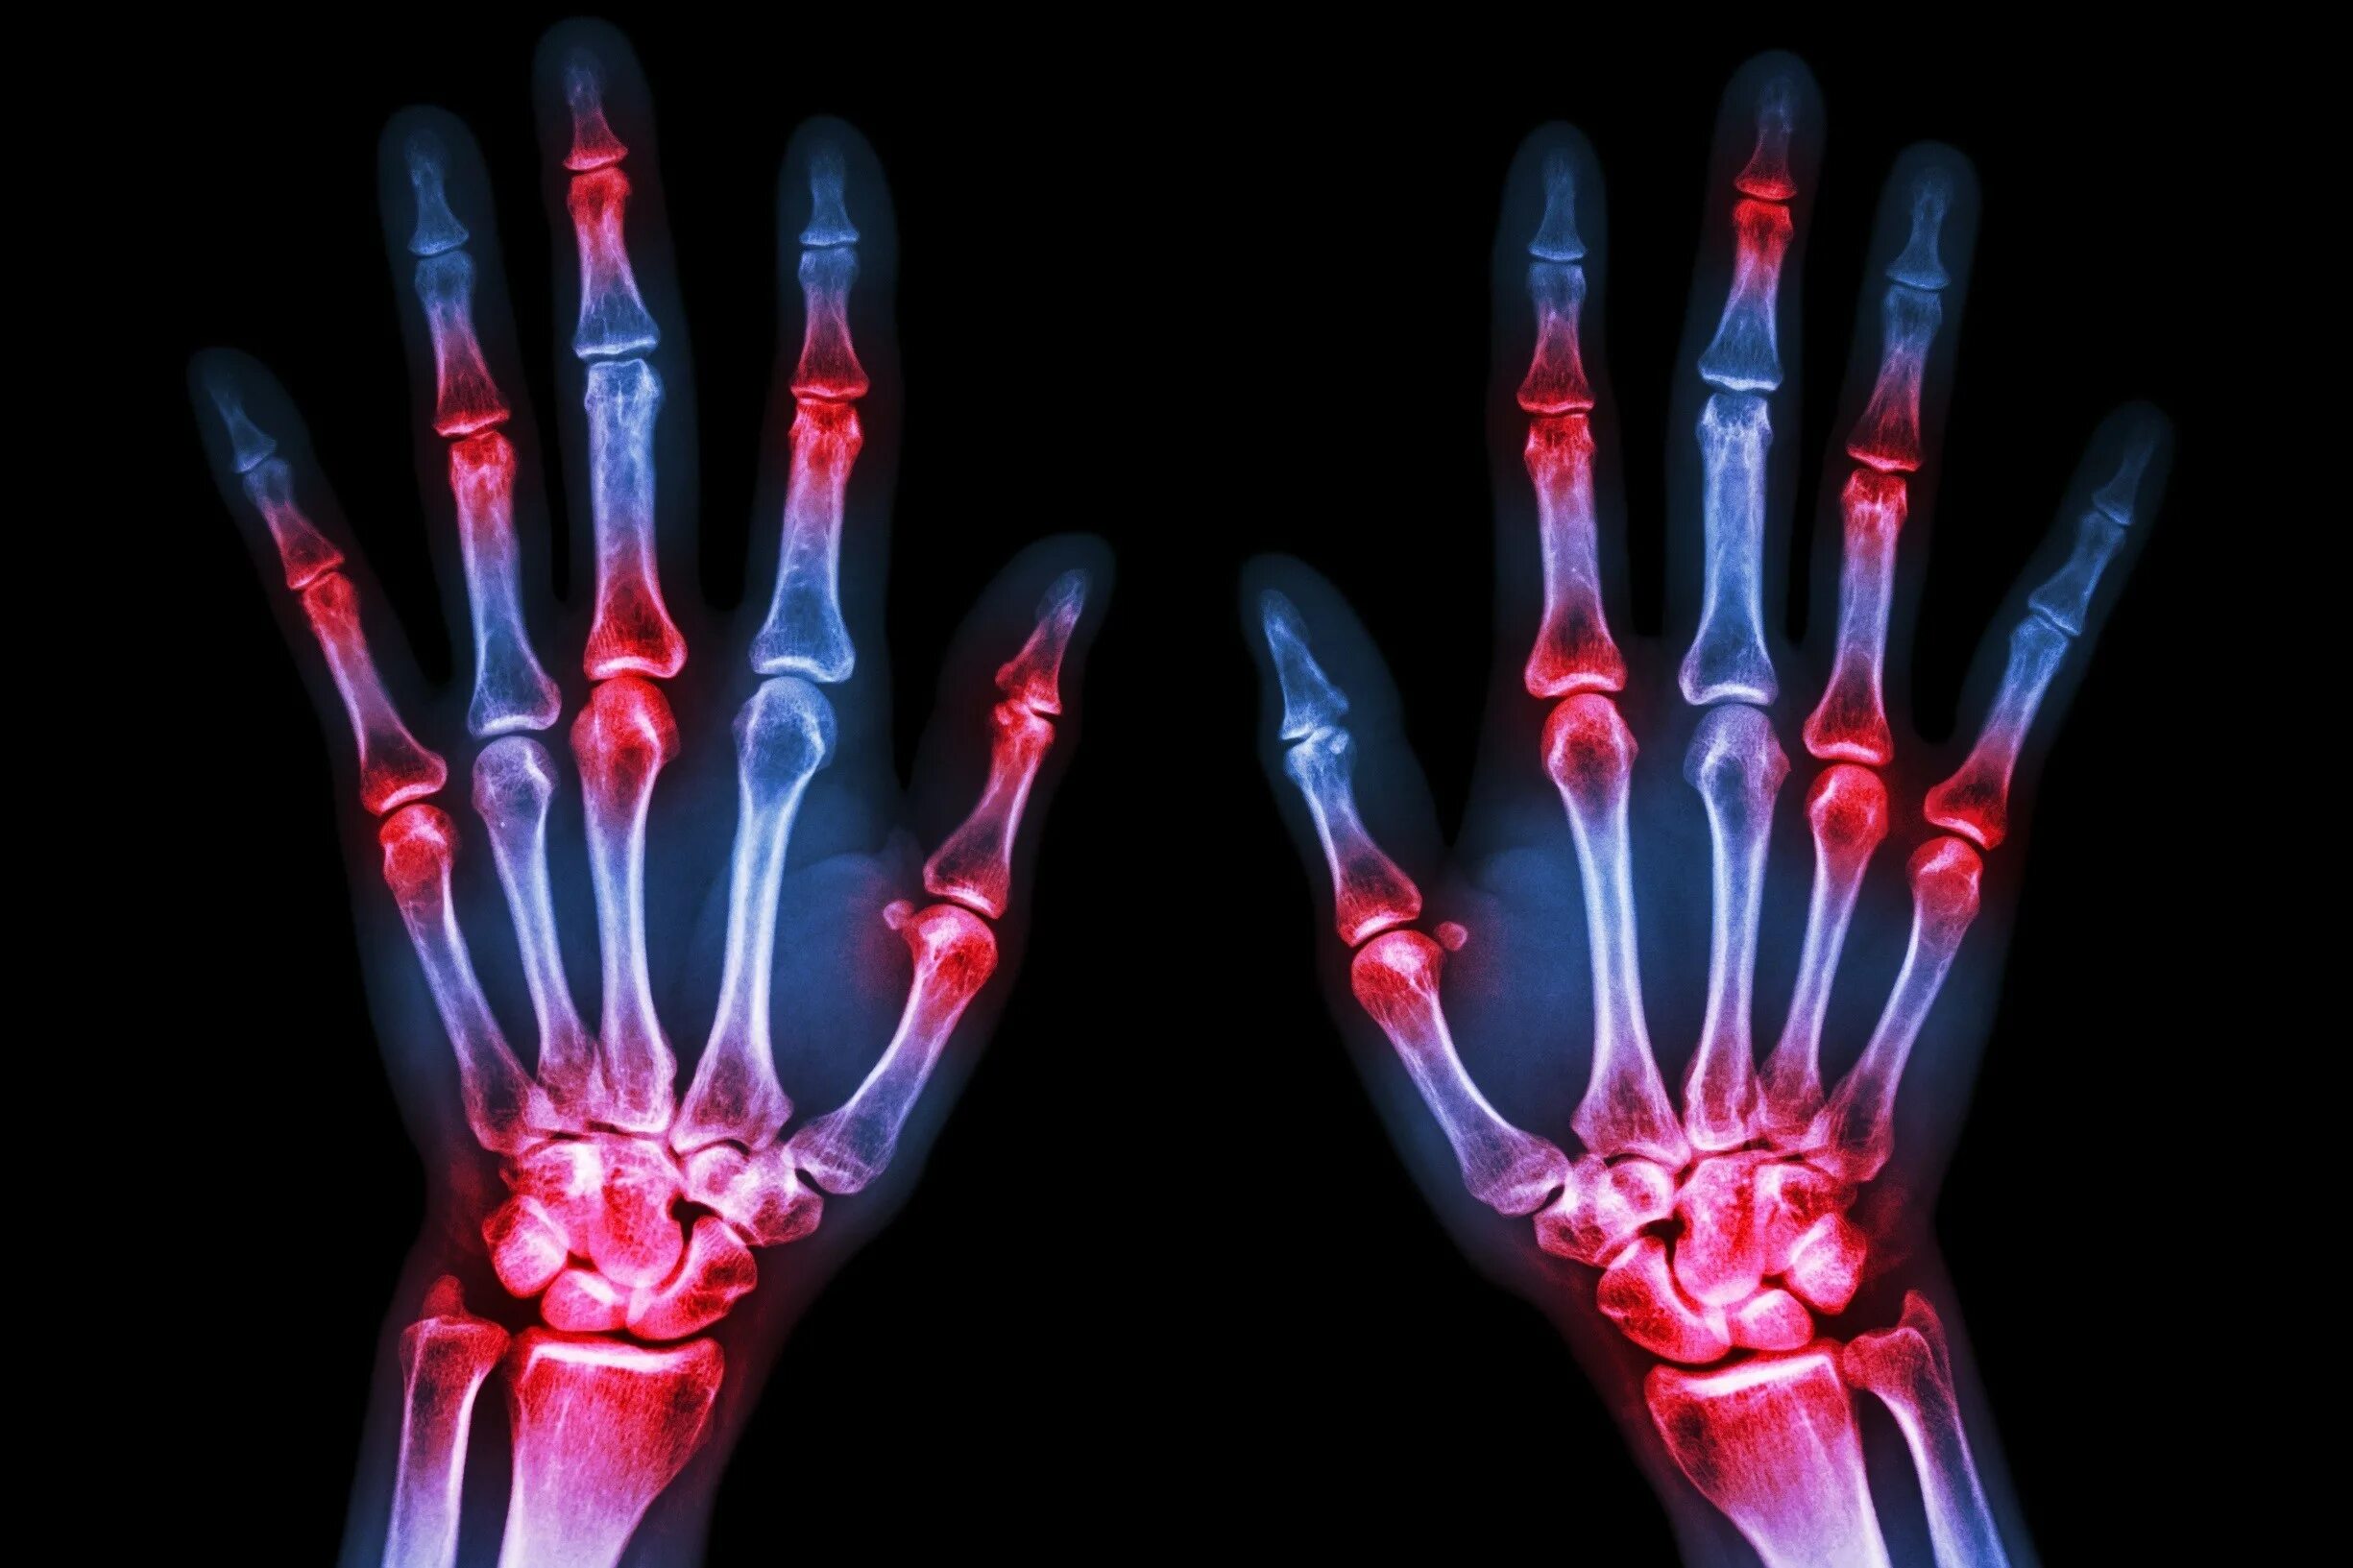

Ревматология артрит